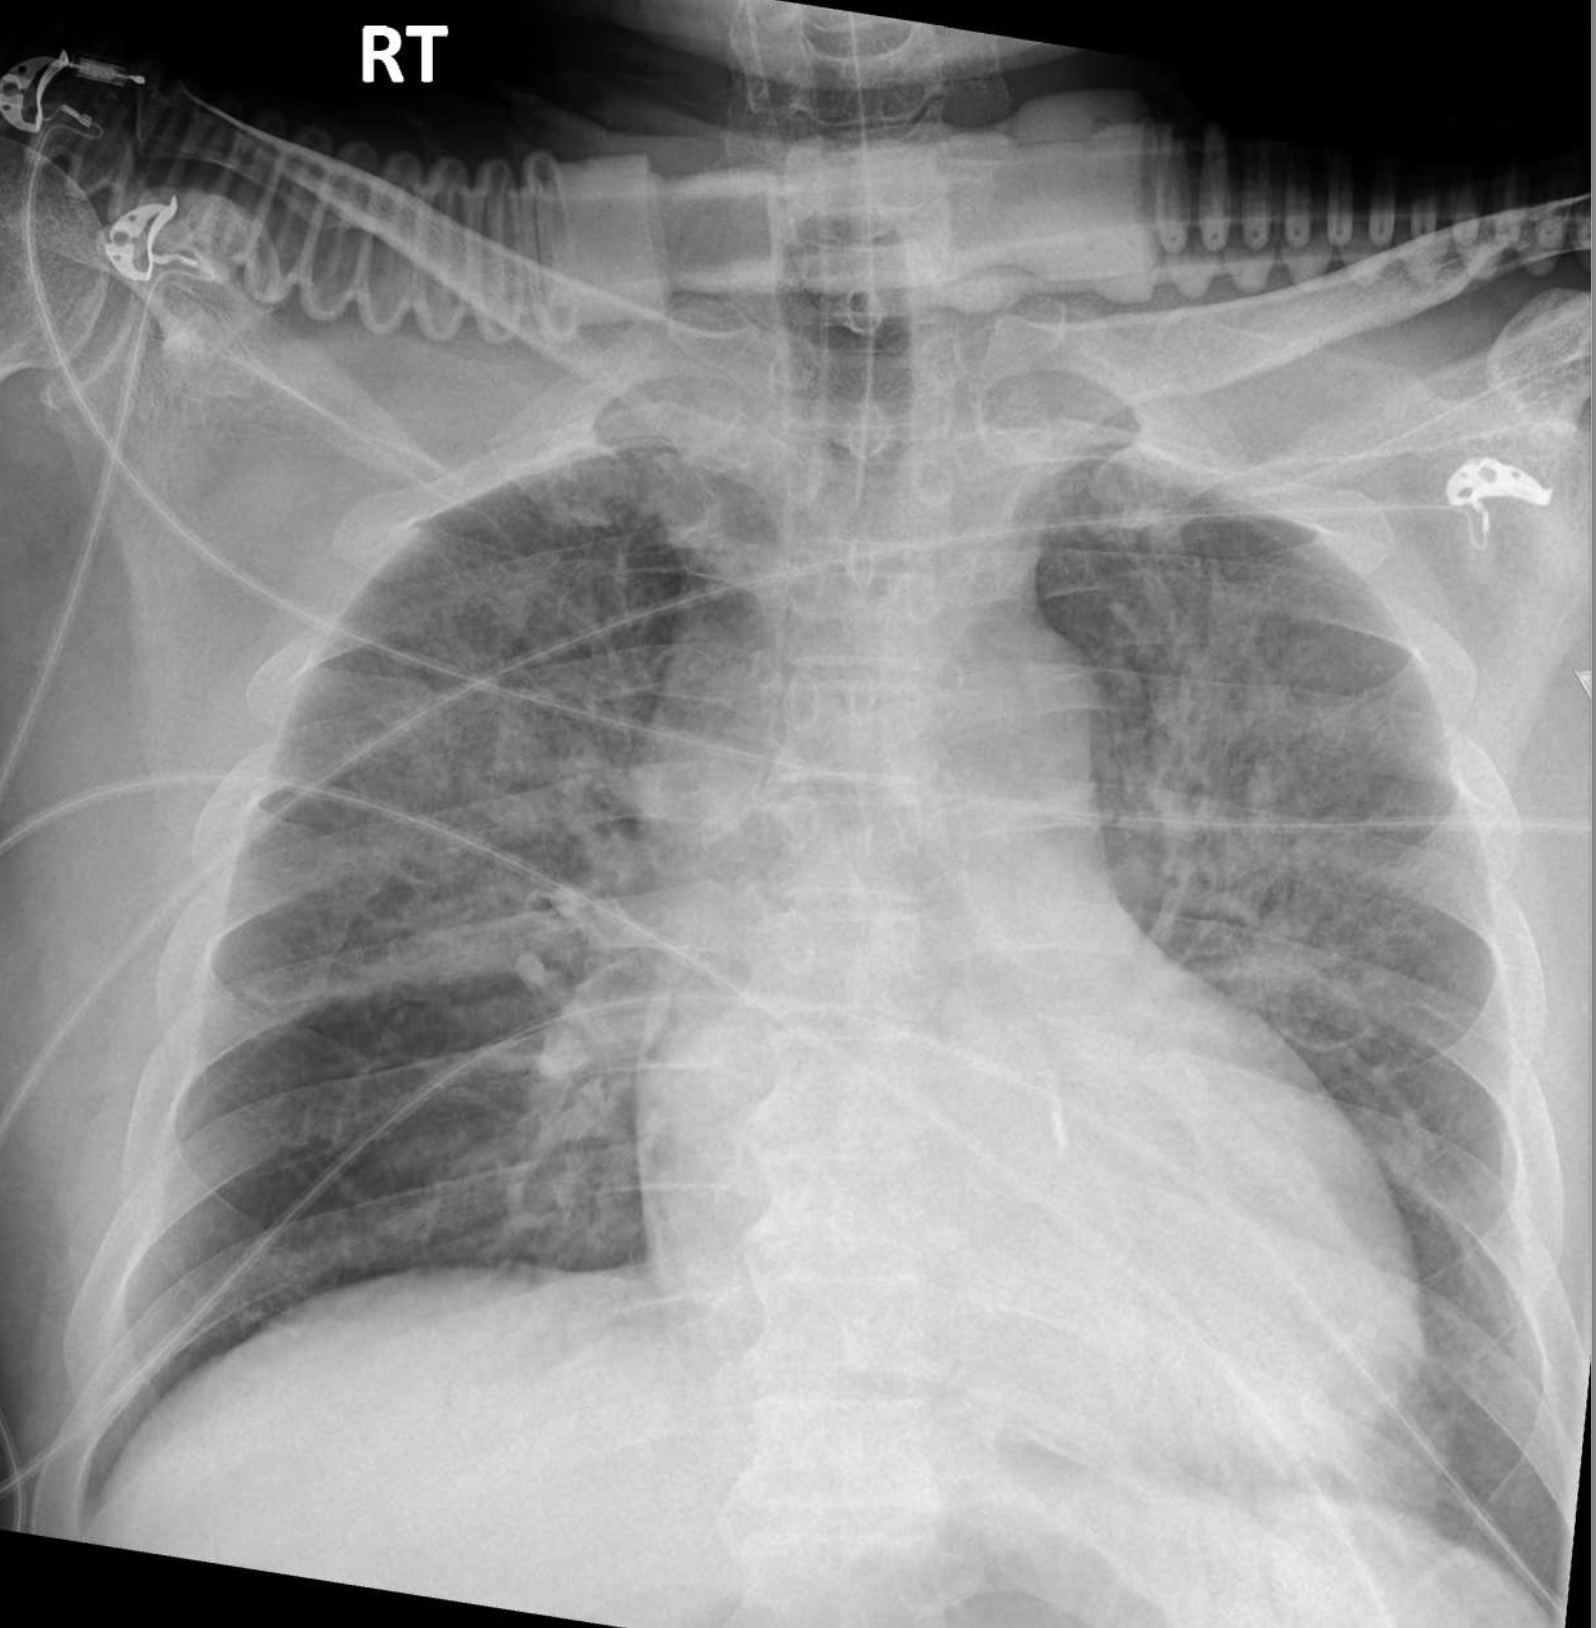

A 65-year-old Thai male with hypertension presented to the emergency department with acute chest pain and dyspnea. The ECG revealed anterolateral ST-segment elevation, new right bundle branch block, and atrial fibrillation. The emergency physician activated the primary PCI protocol. Prior to transfer to the cath lab, the patient was intubated using rapid sequence induction, and intravenous furosemide was administered. Aspirin and ticagrelor were loaded for dual antiplatelet therapy.

- Echo: LVEF 26.9%, akinesia at anterior, anterosepal & anteroseptal wall from basal to apical LV, no significant valvular heart disease, no intracardiac mass or thrombus- Serum creatinine 1.28 mg/dL (eGFR 55.4 ml/min/1.73sqm) - Hematocrit 44.4%, Hemoglobin 14.3 g/dL, Platelet 315,000/uL - Prothrombin time 16.4 seconds, INR 1.51 - Total cholesterol 256 mg/dL, Triglyceride 171 mg/dL, HDL 34 mg/dL, LDL 175 mg/dL